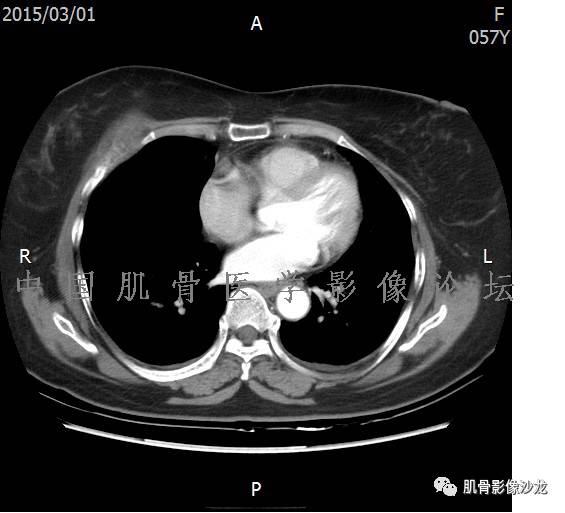

患者2月前无明显诱因下感右腿疼痛、麻木,疼痛呈持续性,发作时无法行走,休息后可缓解。当时无明显肿块,患者遂至当地医院就诊,查X片见右髂骨骨质破坏。6周前患者自觉右髋部渐大肿块,初肿块较小,后肿块逐渐增大,现肿块约12*10cm大小,有压痛。患者遂至我院就诊,查MRI:右髂骨异常信号,伴软组织肿块。ECT、肺CT未见转移。现患者为求进一步治疗,门诊拟“右髂骨肿块 ”收治入院。 患者发病来,神清,精神可,胃纳夜眠可,二便无殊,体重无明显变化。

信号 飞鹰行动:的确应该考虑软骨类肿瘤

飞鹰行动 : 软骨肉瘤内也有纤维组织的

飞鹰行动 : 第一列可以看见T2小结节样高信号,周围有纤维组织环绕

高回青 : 另外还可以见到扇贝状分叶

1、软骨肉瘤可以有膨胀性骨质破坏(病例3,4),可以有溶骨性骨质破坏(病例2),局部皮质因为破坏变薄,中断 ;

2、软骨基质T2WI高信号,软骨小叶分叶状,也就会出现高老师提到的骨内膜扇贝形压迹。一般认为骨内膜扇贝形压迹超过骨皮质厚度的2/3是软骨肉瘤在长管状骨的特征性表现。如上图。3、软组织肿块或肿胀;

4、 钙化,环形,弓形,边缘模糊 ;

5、增强后进行性延迟,不均匀分割状强化, 会强化的纤维间隔,软骨小叶不会强化,关于老师们说到的钙化,软骨肉瘤不一定会有钙化 。